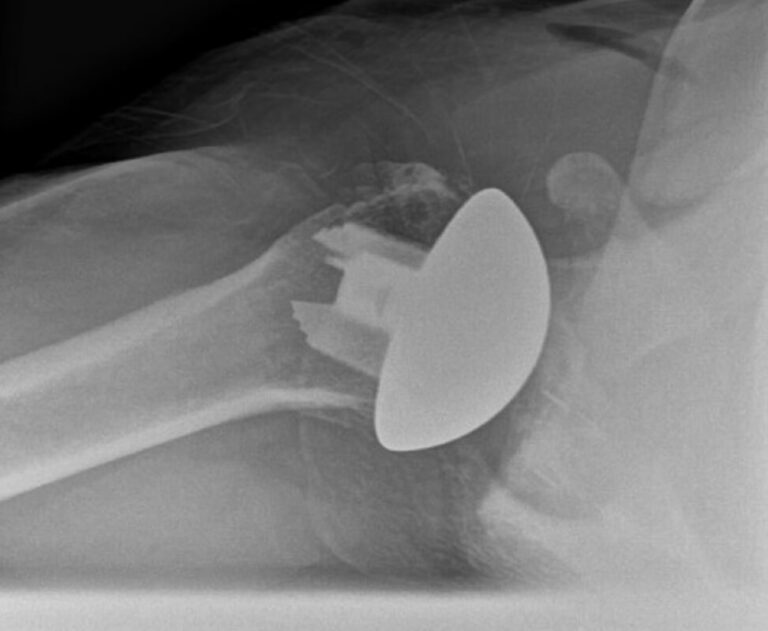

DJO/Enovis, CS Edge